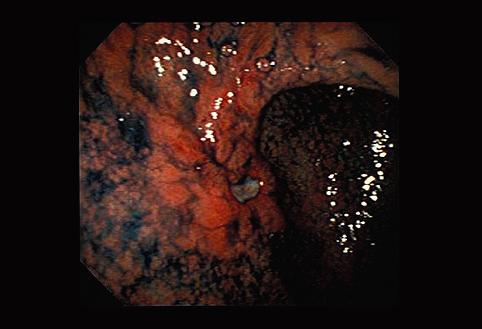

伴有明显纤维化,呈进展期癌样表现的IIc+III型早期胃癌

0型(表在型)/IIc型(IIc+III)

肿瘤最大直径

35~40

肿瘤的深度

m